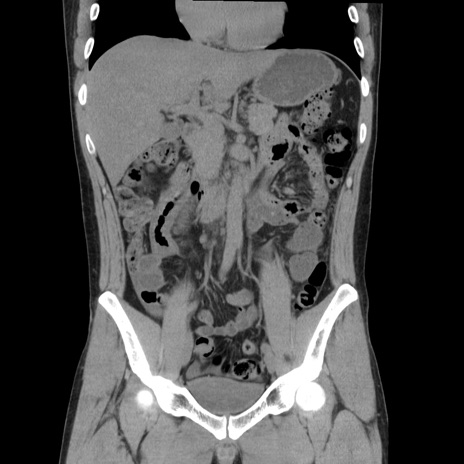

症例36(冠状断像)

【症例】20歳代 男性

【主訴】心窩部痛

【現病歴】今朝より上腹部痛あり。一旦軽快していたが再度出現したため救急要請。昨日夕に白身の魚を含む刺身を食べた。

【身体所見】BP 136/89mmHg、HR 74/min、BT 37.0℃、腹部:膨満、軟、心窩部に圧痛あり。反跳痛なし、筋性防御なし、腸雑音やや亢進あり。

【データ】WBC 17700、CRP 0.48